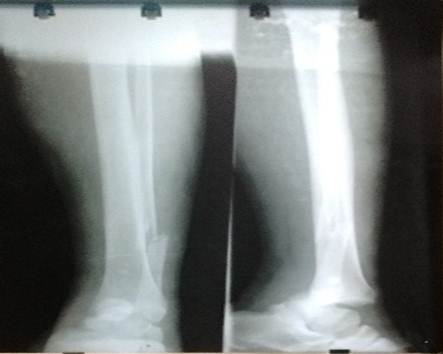

La radiografía simple del tobillo izquierdo en proyecciones anteroposterior y lateral confirmó la presencia de luxación tibio-astragalina (figura 3).